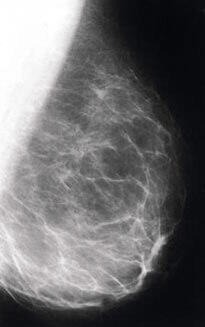

Regardez les récentes recherches conduites par l'Institut national américain du cancer. Ils ont créé un modèle animal fiable pour étudier le cancer du sein et ont trouvé que l'administration de DHEA réduisait significativement l'incidence et la multiplication des tumeurs20. Ici, la note qui est parue dans The Journal of Nutrition : |

La DHEA a même montré une puissante activité anticancéreuse chez des souris préparées pour être hautement sensibles au cancer. Les chercheurs ont également trouvé que les gènes spécifiques qui confèrent cet avantage (incluant p53, DHEA ST et p21) sont stimulés par l'administration orale de DHEA24. |

| Naysayer : Mais ce sont des études animales. Elles ne prouvent pas que la DHEA prévient le cancer du sein chez des êtres humains.

Stephen Cherniske : Je suis d'accord. Mais elles réfutent certainement votre diatribe selon laquelle la DHEA pourrait provoquer le cancer du sein. Il n'y a aucune preuve indiquant que la DHEA augmente le risque de cancer du sein. En fait, une étude publiée dans le prestigieux journal The Lancet a montré une remarquable corrélation entre de faibles niveaux de DHEA et le risque de cancer du sein27. |